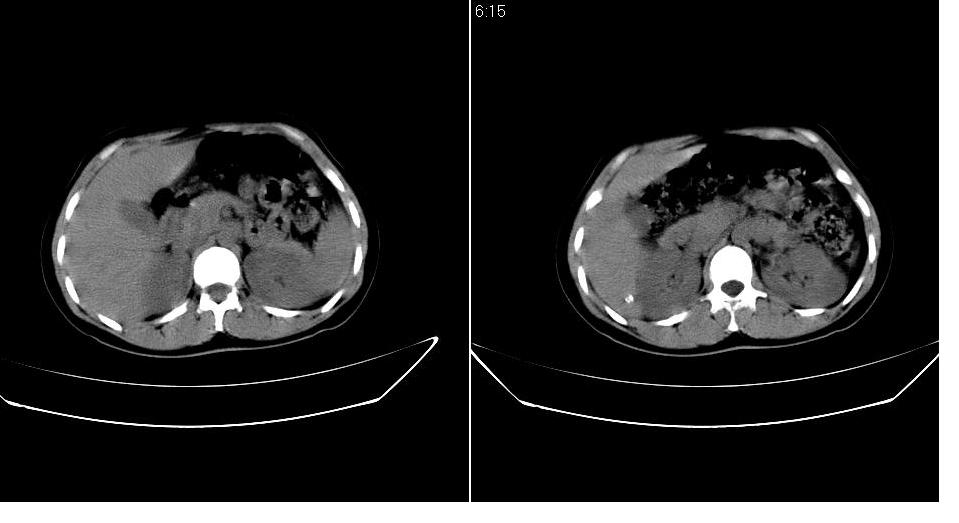

以下是引用求知若渴在2007-9-10 20:08:00的发言:[br]病变以脂肪成分为主,应该是错构瘤。另肝内胆管结石

以下是引用xulianj在2007-9-10 20:51:00的发言:[br]错构瘤,支持。含脂肪成分较多,证明较为成熟。

以下是引用齐原在2007-9-10 20:10:00的发言:[br]病变以脂肪成分为主,应该是错构瘤。另肝内胆管结石

以下是引用王仕学在2007-9-10 21:34:00的发言:[br]有脂肪密度,哪怕是一点点,首先考虑错构瘤。还是增强吧,好说些!